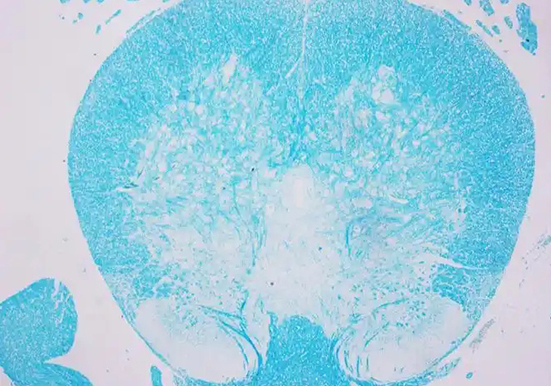

LFB 染色

LFB 染色即劳克坚牢蓝(Luxol Fast Blue)染色,是一种常用于显示神经组织中髓鞘结构的染色方法,以下是关于它的详细介绍:染色原理:LFB 属于铜 - 酞箐染料,是一种酒精溶···